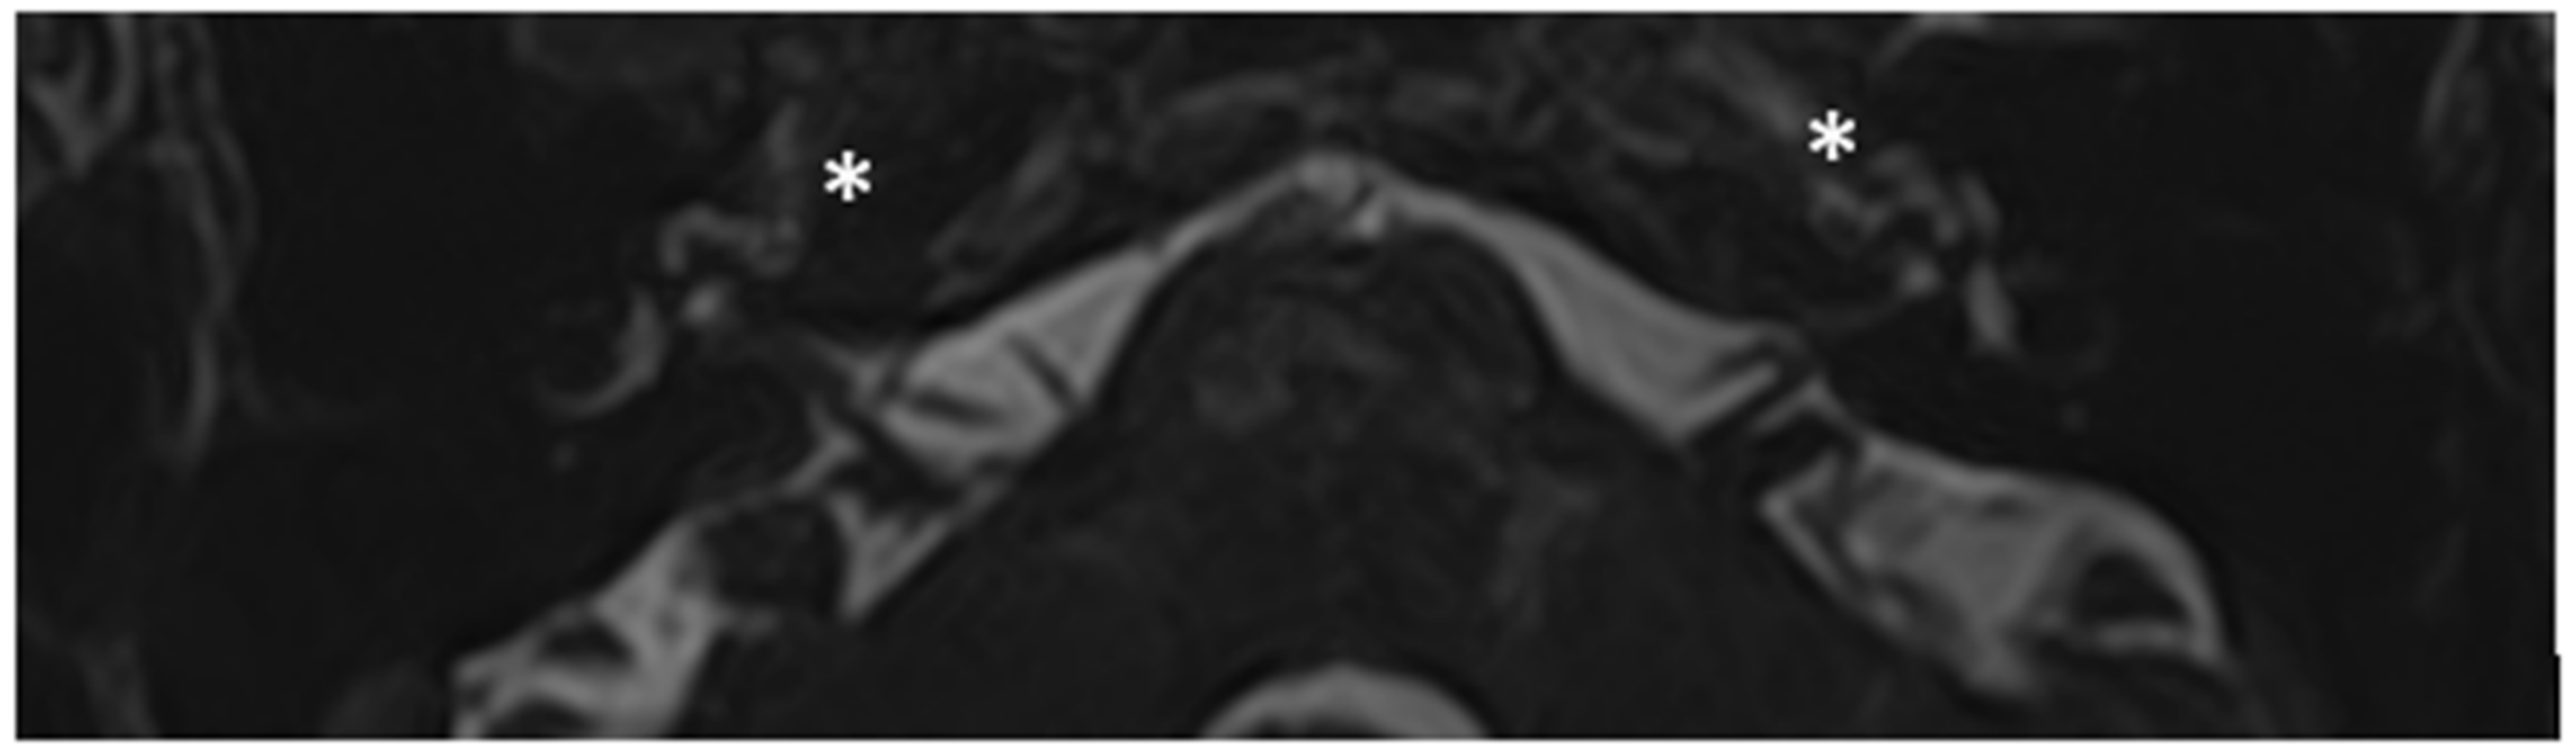

Within a few years, both ears showed a worsening of bone threshold to SNHL bilaterally. In 2017 (27 years since diagnosis) she developed profound SNHL with left-sided anacusis and underwent cochlear implantation in the left ear. CT and MR images showed a large cavity around the basal turn of the cochlea and massive osteorarefaction around the cochlea (‘double ring’ sign). The cavity appeared to contain cerebrospinal fluid but did not communicate with the cochlear lumen (Figure 1 and Figure 2).

Figure 1. CT images of patient #1 with osteogenesis Imperfecta. (A,B), right side in axial plane. (C,D), right side in coronal plane. (E,F), left side in axial plane. (G,H), left side in coronal plane. A pericochlear cavity is visible in all figures; arrows indicate its origin from the IAC. Asterisks indicate extension of osteorarefation into the cochlea.